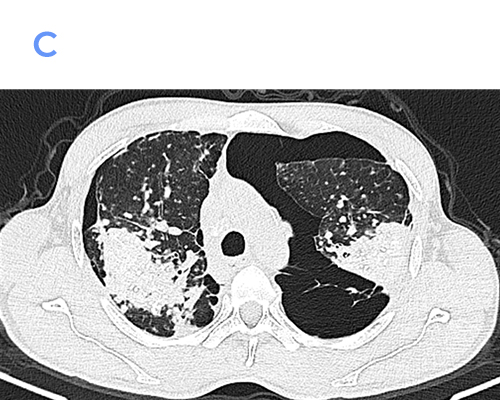

Computed Tomography (CT)

• Numerous well-defined centrilobular and perilymphatic nodules in the upper lobes.

• Conglomerate fibrotic masses with irregular margins and variable internal calcification.

• Traction bronchiectasis and bronchiolectasis adjacent to fibrotic areas.

• Marked architectural distortion with posterior and superior displacement of fissures.

• Enlarged hilar and mediastinal lymph nodes, frequently showing peripheral (“eggshell”) calcification.

• Areas of emphysema, especially adjacent to fibrotic masses.

CT is superior in detecting early PMF, subtle nodal calcifications, and complications such as superimposed infection or lung cancer.